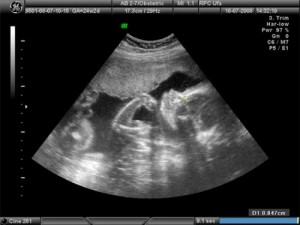

Возраст плода - 34 недели (от момента зачатия) и 36 недель от первого дня последних месячных.

Вес малыша - около 2,6-2,8 кг, рост - 46-48 см, от макушки до копчика - 34 см. Вес может значительно колебаться, не стоит подстраиваться под стандарты мерок.